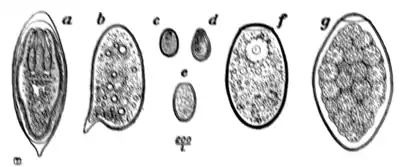

Fig. 168.—Ova of nematodes.

a, Strongylus subtillis; b, Ankylostomum duodenale; c, Trichiuris trichiura; d, Strongyloides starcoralis; e, Necator americanus; f, Ascaris lumbricoides; g, Ascaris lumbricoides (unfertilized).

rarely found in the stools, as these parasites do not, as a rule, part with their ova until the joints of the former, or the entire body of the latter, have left the alimentary canal; but as the three nematodes first mentioned pass their eggs directly into the bowel, these eggs habitually appear in the fæces and constitute unequivocal evidence of the presence of their respective parental forms. Occasionally the ova of hepatic and intestinal parasites, such as Schistosomum japonicum, S. mansoni, Clonorchis sinensis, Fasciola hepatica, Fasciolopsis buski, and other rarer helminths, are encountered. Without large experience the ova of the rarer parasites cannot be identified off hand; but if the practitioner has learned to recognize those of the three common species, he will at one know when he comes across the ova of any of the rarer species, and, on referring to some special work on helminthology, will have little difficulty in arriving at a correct diagnosis.

The points to be attended to in the diagnosis of ova are size, shape, colour, thickness, roughness, smoothness, and markings on the surface of the shell; the presence or otherwise

of yolk spheres, of a differentiated embryo, or, in the case of the cestodes, of the three pairs of embryonic hooklets; the existence of an operculum in the case of certain trematodes and of the broad tapeworms (Dibothriocephalus). The ova of the same species of parasite vary but slightly, and are in every instance sufficiently stable and definite for correct diagnosis.

Ova of Trichiuris trichiura (Fig. 168, c).—Of the three common nematodes mentioned—Trichiuris trichiura, Ascaris lumbricoides, and Ankylostomum duodenale—the ova of the first are the most frequently met with. They occur sometimes in enormous numbers, as many as six or eight specimens being visible in one field of an inch objective. They form a rather striking object under the microscope (Fig. 170). They are oval, measuring 51 to 54 μ by 21 to 23 μ, the ends of the long axis of the oval being slightly pointed and tipped with a little shining projection or plug. Their general appearance suggests an elongated oval tray, the projections at the poles of the ovum representing the handles of the tray. They are dark brown in colour, sharply defined, doubly outlined, and contain no differentiated embryo.

The ova of Ascaris lumbricoides (Fig. 168, f, g, and Fig. 171) are considerably larger (60 to 75 μ by 40 to 58 μ) than those of trichiuris (Fig. 168, c). They are also, as a rule, more spherical, or rather, more broadly oval; occasionally they are almost barrel-shaped. Like those of trichocephalus, they are dark brown in colour from bile-staining, but they are much less sharply and smoothly defined, possessing a coarse thick shell which is roughened by many warty excrescences. The yolk contents are not always easily made out, nor, when made out, can any sign of embryo or segmentation be discovered.

In certain instances, supposed to be unfertilized, the ova are smooth on the surface, the rough outer layer being almost or altogether absent.

A point of practical importance to be attended to lies in the circumstance that the rough outer layer on the shell of the ovum of ascaris is very easily detached, leaving the egg with a sharp, smooth outline suggestive of some other species of parasite. To obviate this, in mounting fæces it is well to avoid too much gliding of the cover-glass over the slip.

The ova of Ankylostomum duodenale (Fig. 168, b) contrast very markedly with both the foregoing, particularly in the matter of colour. Trichocephalus and ascaris ova are invariably dark and bile-stained; those of the ankylostomum are beautifully clear and transparent; they measure 55 μ to 65 μ by 32 μ to 43 μ; have a regular, somewhat elongated oval form, with a delicate, smooth, transparent shell, through which two, or four, or eight light-grey yolk segments can be distinctly seen. It is well to search for these ova soon after the fæces have been passed; otherwise, owing to the rapidity with which, in favourable circumstances, development proceeds, the embryo may have quitted the shell and the egg be no longer visible.